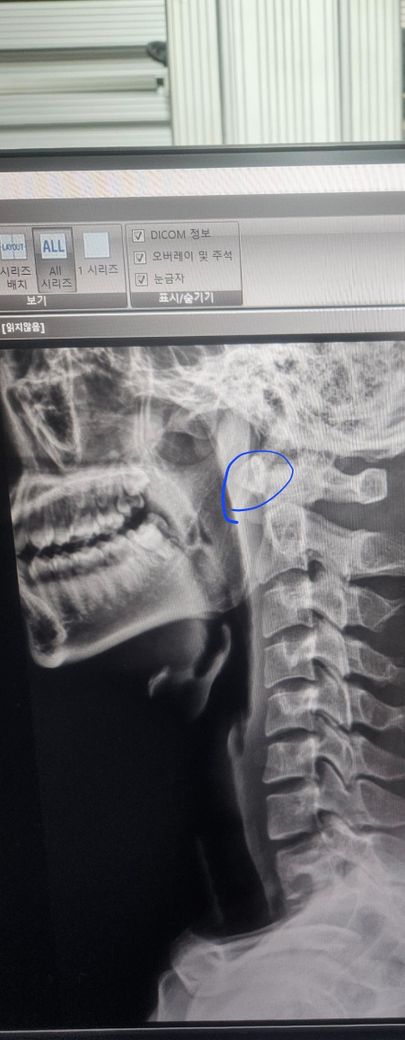

경추 동그라미 친 부분 이부분 뭔가요??

제목 그데로 입니다 저부분이 유난히 올라가 있는거같고 뭔가 궁금해서 올려 봅니다 다른 분들도 다 있는데 저만 그런건지 동그라미 친부분이 쫌 위쪽에 있는것같아서요

엑스레이상 동그라미 치신 부분은 경추 1번 목뼈의 앞부분으로 해부학 구조상으로는 약간 올라간 형태를 뛸 수는 있으며 그 이유로는 경추의 곡선이 약간의 c커브를 가지고 있기 때문이며 엑스레이 사진상으로는 큰 문제는 없는 것으로 보입니다.

질문자분께서 올려주신 사진의 동그라미로 표시해주신 부분은 경추 1번의 앞쪽입니다. 해부학 구조상으로 약간 올라간 형태를 띌 수 있는데요, 경추의 곡선이 약간의 C커브를 가지고 있기 때문입니다. 별다른 문제는 없으신 것으로 보입니다.